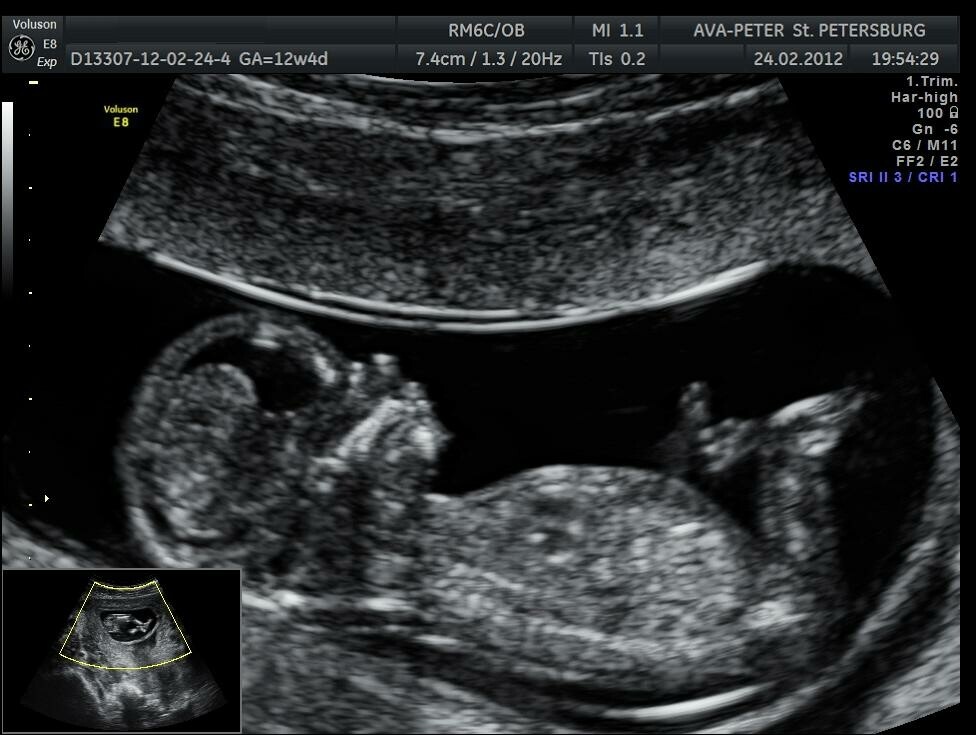

Почему вредно делать УЗИ при беременности

Аппарат посылает высокочастотные звуковые волны и анализирует то, как они отражаются. По этим данным строится изображение. На экран выводится картинку, оценивая которую, доктор может судить о состоянии того или иного органа в теле человека.

Иногда в сети пишут, что частые УЗИ могут вредить ребенку или говорят, что именно 3D-режим опасен. В реальности же 2D/3D/4D УЗИ полностью безопасно для ребенка. Это доказано множеством исследований.